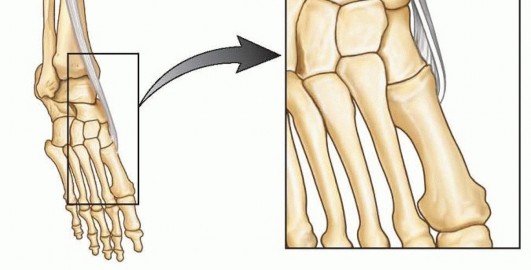

Anterior tibialis tendon transfer does not correct restricted subtalar motion.It is important to confirm that the ossific nucleus of the lateral cuneiform is present in order to place the anterior tibialis tendon into an appropriate anchor site. ## Positioning The patient is placed in the supine position on a standard operating table or the legs draped over a hand table.Either positioning is done in a way to ensure good fluoroscopic images.A well-padded, thigh-high tourniquet should be placed before preparing and draping the patient. ## Approach A medial incision is based over the insertion of the anterior tibialis tendon.From this incision, the surgeon may be able to perform an opening wedge osteotomy of the medial cuneiform if indicated.Once the anterior tibialis tendon is detached, a lateral incision is based over the lateral cuneiform. Fluoroscopic imaging can assist in planning this incision.The lateral incision may need to be longer and more laterally based should the surgeon decide to perform a cuboid closing wedge osteotomy at the same time. ## TECHNIQUES 1. ## Full Anterior Tibialis Tendon Transfer to the Lateral Cuneiform 5, 11 ### Approach A 4-cm long dorsal-medial longitudinal skin incision is made over the course of the anterior tibialis tendon from the inferior margin of the ankle retinaculum (the superior limb of the inferior extensor retinaculum) to its palpable distal insertion based over the medial cuneiform ( TECH FIG 1).Dissection is carried down through subcutaneous tissues and the inferior limb of the inferior extensorretinaculum to expose the tendon sheath.The anterior tibialis tendon sheath is incised sharply and opened as far distally as possible and then proximally to just short of the ankle retinaculum.A hemostat is placed under the anterior tibialis tendon to help expose the insertion.This broad extensive insertion is detached as far distally as possible to gain maximum length of tendon for the transfer.It is critical to obtain as much length as possible. Illustration 10 for Why Anterior Tibialis Muscle Transfer Fixes Clubfoot --- Illustration 11 for Why Anterior Tibialis Muscle Transfer Fixes Clubfoot ### TECH FIG 1 • A. Two incisions are made. B. The medial incision is made over the course of the tibialis anterior tendon. The surgeon frees the tendon from its broad insertion as far distally as possible and proceeds proximally as far as the ankle retinaculum. * Transferring the Tendon Once the tendon is freed and detached distally, a strong absorbable suture (eg, 1-0 Vicryl) is woven in a Bunnell-type fashion through the anterior tibialis tendon.Care is taken to weave the suture in a fashion that does not lead to a bulbous end, thus making the tendon difficult to deliver to the lateral wound and subsequently pass into the lateral cuneiform.Occasionally, the loose ends of the tendon insertion are trimmed or incorporated with a 3-0 absorbable suture to facilitate passage and anchoring.By pulling on the suture, the tendon is gently pulled distally while the soft tissue attachments to the tendon are freed up to, but not beyond, the ankle retinaculum.To avoid bowstringing of the tendon, it is important not to release the ankle retinaculum. A dorsal-lateral longitudinal incision, 1.5 to 2 cm long, is made over the lateral cuneiform.The lateral cuneiform is identified just proximal to the base of the third metatarsal.

Dissection is carried down through subcutaneous tissues to the toe extensors.To expose the lateral cuneiform, the toe extensors are retracted medially and the extensor digitorumbrevis muscle is retracted laterally.A cruciate periosteal incision is made directly over the lateral cuneiform, carefully avoiding the adjacent joint articulations.In young children, a Keith needle is used to fluoroscopically locate the center of the ossific nucleus.In older children, a small periosteal elevator is used to elevate the periosteal flaps off the lateral cuneiform.Occasionally, these flaps may be sutured into the transferred tendon, thus supplementing fixation. In young children, however, it may be difficult and futile to elevate perichondrium from the predominantly cartilaginous bone.A blunt hemostat is then passed from the lateral incision over the lateral cuneiform and under the extensor tendons to the point where the anterior tibialis tendon passes beneath the ankle retinaculum.Use the hemostat to develop a tract for the transfer of the anterior tibialis tendon.The hemostat is passed into this same tract into the medial wound to grasp the suture ends and bring the anterior tibialis tendon into the lateral wound ( TECH FIG 2).Ensure that the available length of the tendon will reach the proposed transfer site into the lateral cuneiform. ### Attaching the Transferred Tendon A drill bit is selected to be slightly larger than the diameter of the sutured anterior tibialis tendon end.Once the bit is selected, make a hole directly in the center of the lateral cuneiform, drilling just through the plantar aspect of the bone (dorsal to plantar while aiming for the arch of the foot).The suture ends of the tendon are threaded onto Keith needles ( TECH FIG 3A).While the foot is maximally dorsiflexed and everted, the suture needles are passed through the lateral cuneiform drill hole and out through the plantar aspect of the foot, guiding the tendon through the drill hole. Illustration 12 for Why Anterior Tibialis Muscle Transfer Fixes Clubfoot --- Illustration 13 for Why Anterior Tibialis Muscle Transfer Fixes Clubfoot ### TECH FIG 2 • The freed anterior tibialis tendon is brought into the lateral wound. The tendon is confirmed to easily and reproducibly slide into its new insertion.This is a critical step: Be certain that the tendon reliably enters the anchoring hole after the skin is closed when the foot is dorsiflexed and when the suture is tensioned. Smooth passage of the tendon into the third cuneiform may be facilitated by a drop or two of sterile mineral oil.The suture needles on the plantar aspect of the foot are passed through a nonadhesive dressing (eg, Adaptic) and a sterile felt pad.At this time, it is advisable to irrigate and close all other associated wounds, leaving the lateral recipient wound for last.This way, the surgeon can ensure that the anterior tibialis is in the intended position just before dressing and cast application.The periosteum of the lateral cuneiform is sutured with two interrupted absorbable sutures to the transferred anterior tibialis tendon while it is pulled into the recipient site ( TECH FIG 3B).The lateral wound is irrigated and closed in layers while the foot is held in a dorsiflexed position, thus ensuring that the anterior tibialis remains in the hole and the continuity of the periosteal sutures is preserved.Sterile dressings are applied while an assistant simultaneously maintains the foot dorsiflexed with tension on the suture.The distal foot and ankle portion of a toe-to-groin cast is applied while ensuring that the suture ends of the tendon are in tension.In the past, we have tied the button over the felt underneath the cast. However, a high rate of pressuresores has led us to consider alternative fixation.After the cast is hardened, the suture is tied over a button on the exterior of the plantar aspect of the cast ( TECH FIG 3C).To prevent plantar pressure sores, make sure the plaster is sufficiently hardened. Commercially available suture anchors can also be used to facilitate fixation of the tendon.Some surgeons will perform the exact procedure except transfer the whole tendon into the cuboid. These surgeons choose this